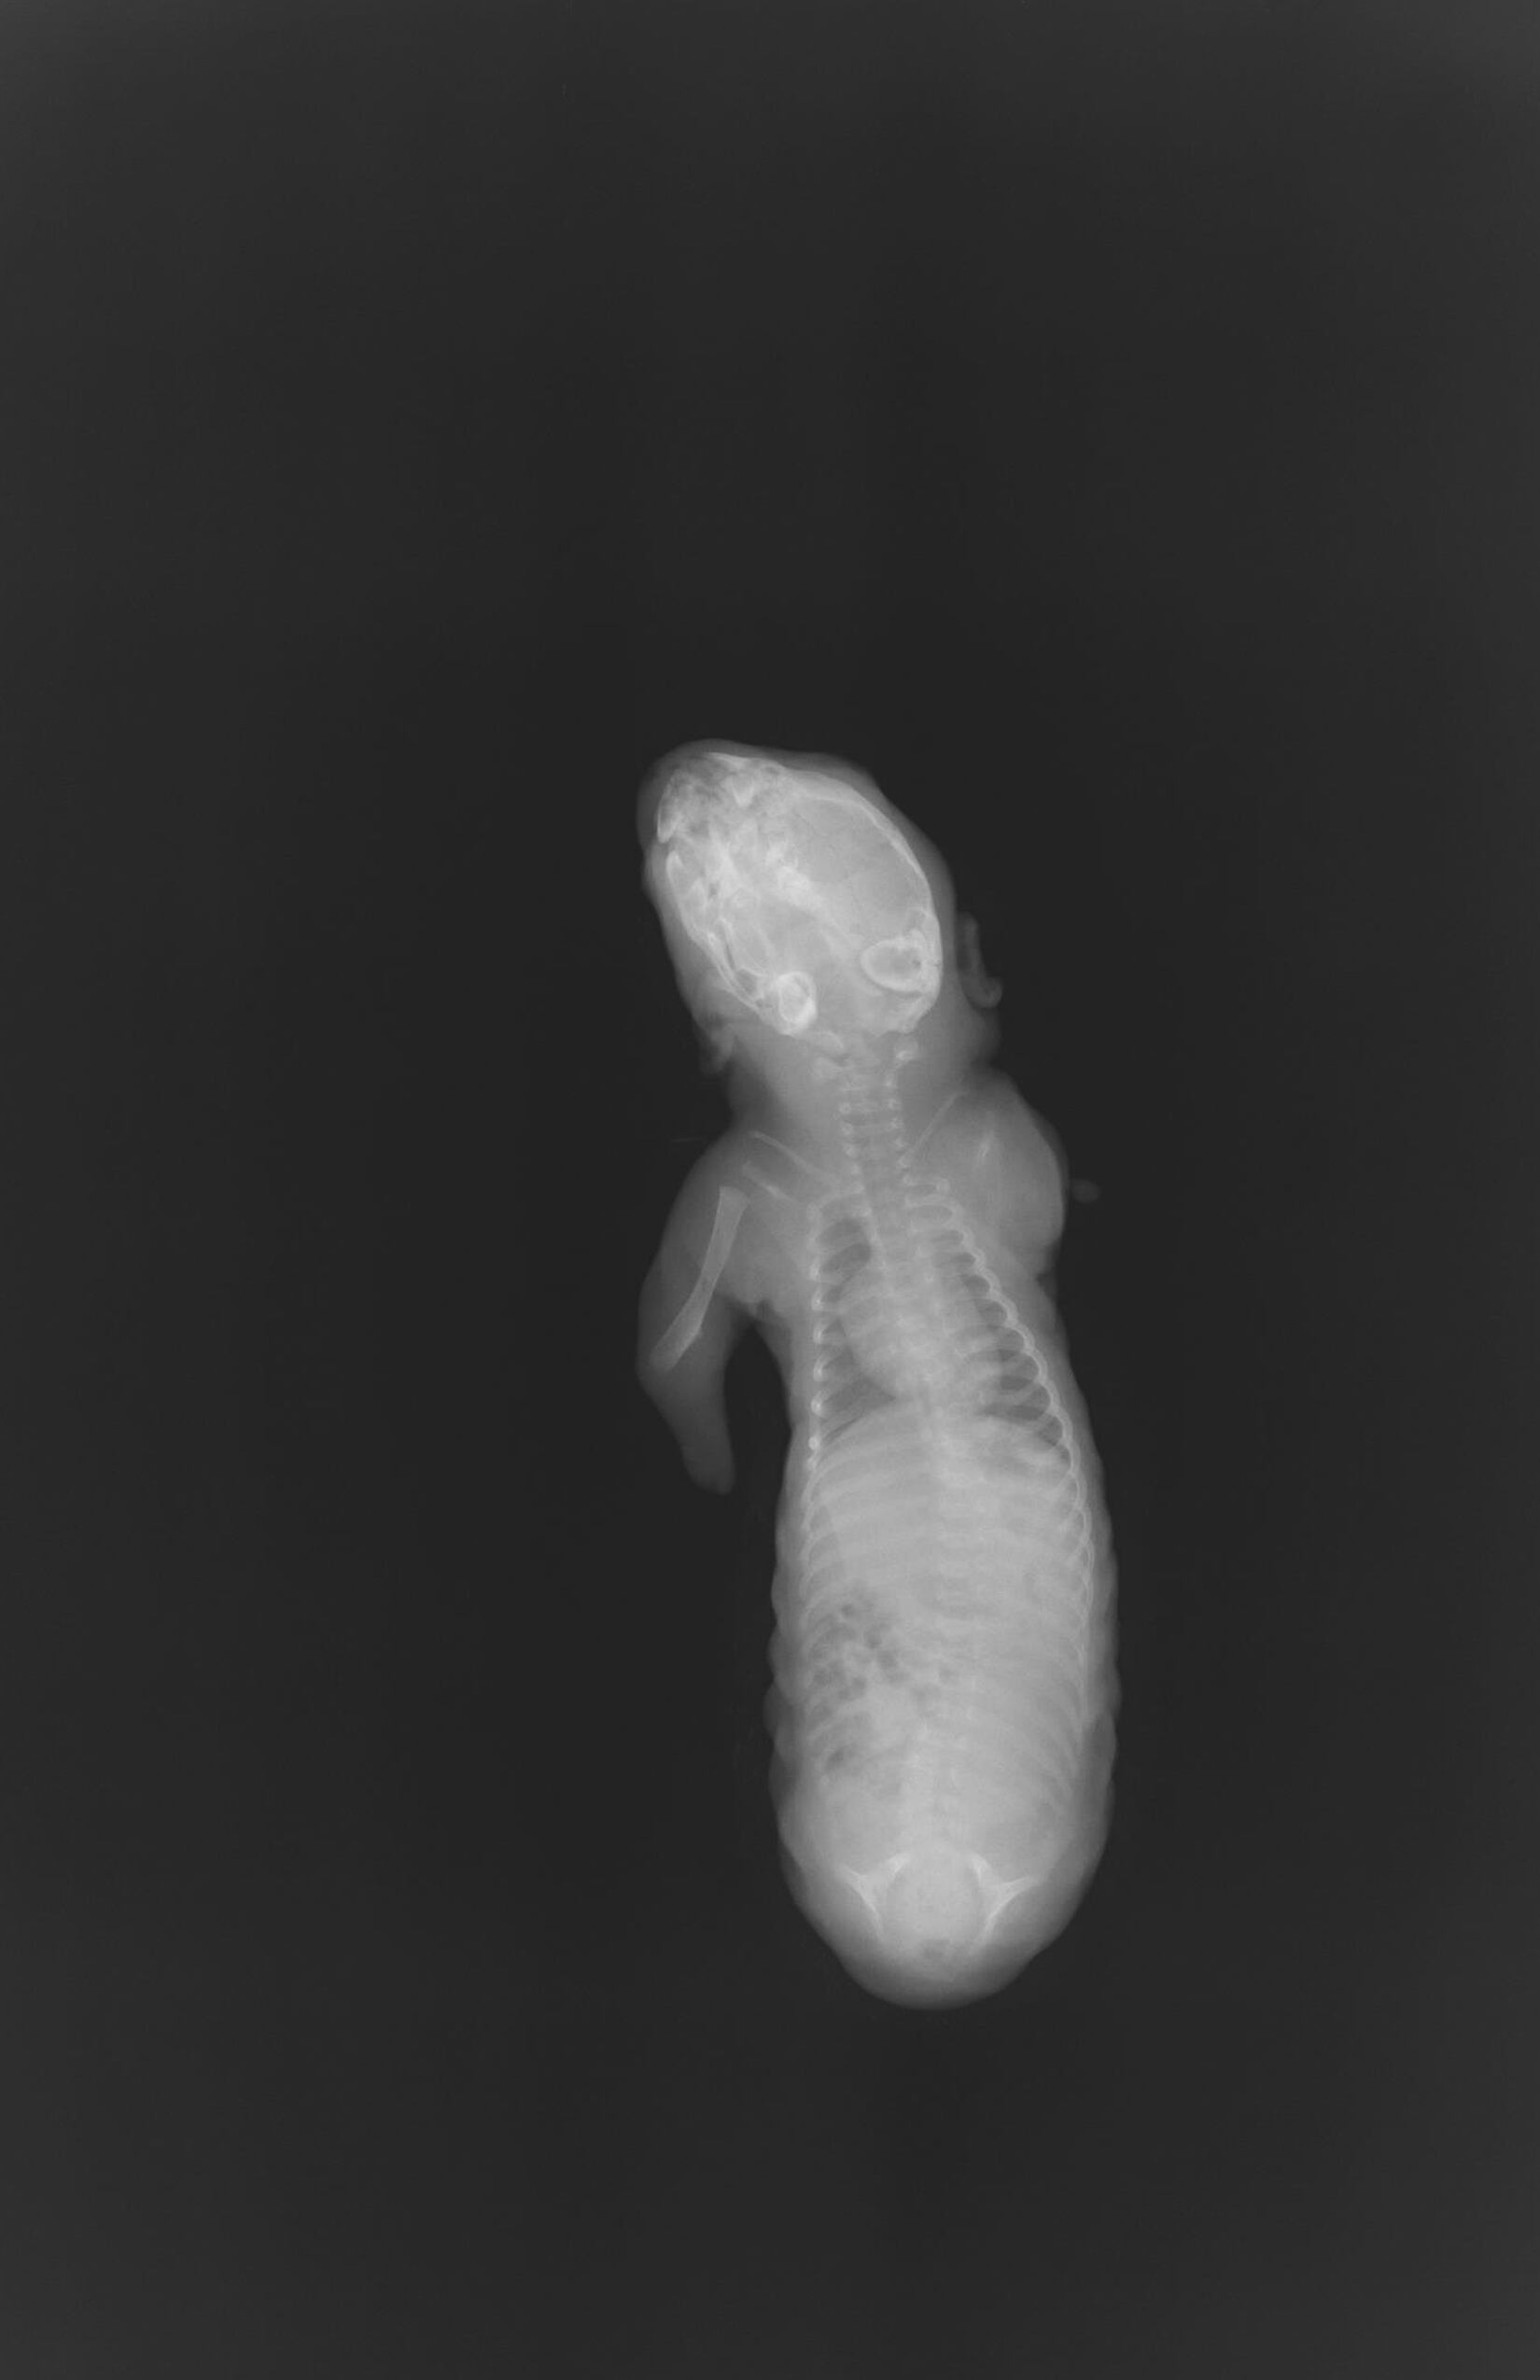

Los más indefensos también padecen. Le pasó a un bebé perezoso, que apenas contaba con el húmero, ese hueso largo y fundamental para el movimiento del brazo. Los especialistas sospechan que fue víctima de contaminación por pesticidas, debido a que su madre habitaba una zona dominada por cultivos de palma africana, donde frecuentan las fumigaciones.